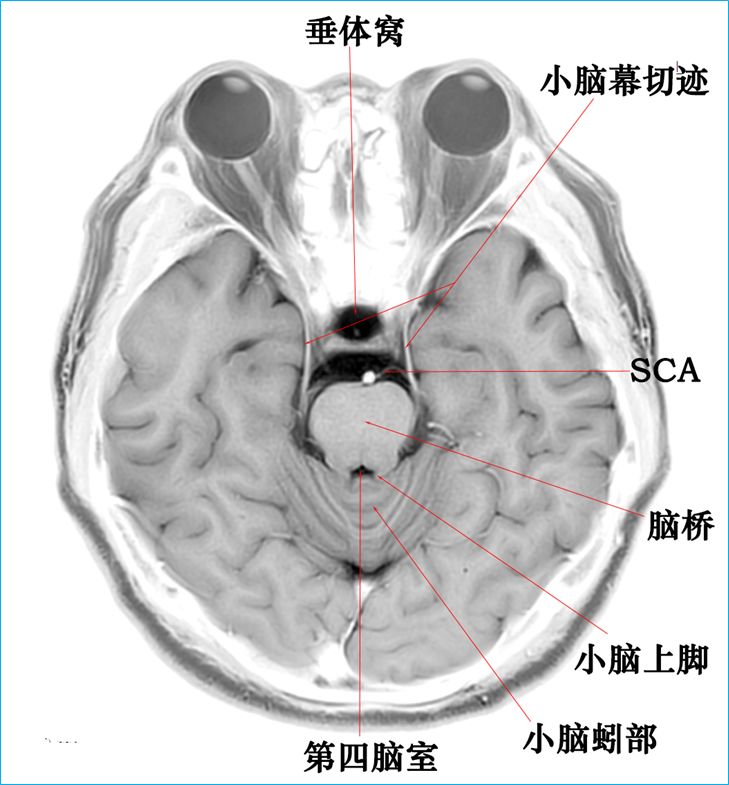

在T2WI反相图学下的颅脑断层解剖(吴老师亲自手动标准)以及标本断层解剖,满满干货,坐在小板凳上,一起学习吧...

3.0T-T2WI反相图学颅脑断层解剖

大脑半球标本连续切片断层解剖

作者:吴晓安仅供学习交流